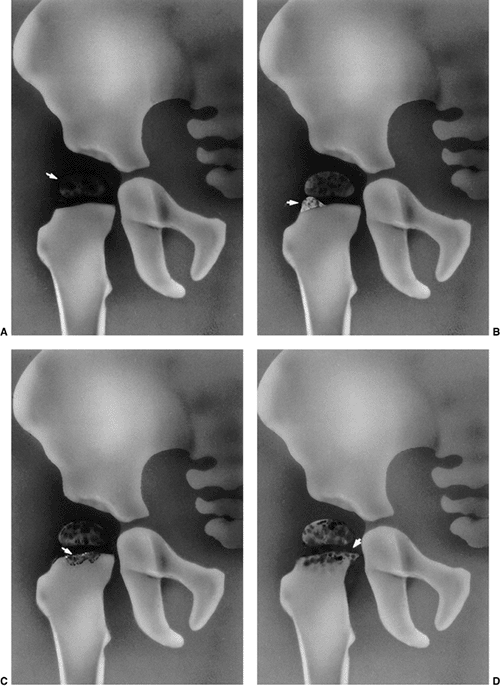

![]() |

Figure 24.8 A:

Right acetabular cavity and femoral head of a newborn baby with bilateral congenital hip dysplasia. There is an acetabular bulge (B) or neolimbus along the upper acetabular cartilage, and the acetabular cavity is small. B: Frontal section of the same hip. The femoral head is very large in relation to the acetabular cavity. Note how the labrum is everted and adheres to the joint capsule above. The neolimbus (B) is composed of hypertrophied acetabular cartilage. (From Ishii Y, Weinstein SL, Ponseti IV. Correlation between arthrograms and operative findings in congenital dislocation of the hip. Clin Orthop 1980;153:138.) |

cases, accessory centers of ossification contribute to acetabular development (Fig. 24.9). Accessory centers of ossification

appearing 6 months to 10 years after reduction (34,35,36,37,44) (Fig. 24.9). These accessory centers

coalesce to form a normal acetabulum (Fig. 24.9).

Figure 24.9 A:

An 18-month-old girl with bilateral high dislocations. Note the poorly developed acetabula with well-developed secondary acetabula. B: At 33 months of age, the irregular ossification centers in the left and right hip have coalesced, with a slight improvement in the acetabular index. C: When the girl is 7 years of age, an anteroposterior view shows the appearance of the accessory centers of ossification in the periphery of the acetabulum. D: The accessory centers of ossification are somewhat better appreciated in the abduction view at 7 years of age. E: An anteroposterior view at 8 years of age shows the coalescence of the accessory centers of ossification, increasing the depth of the acetabulum. Note the excellent sourcil formation. F: The accessory centers of ossification are well demonstrated in an abduction view at 8 years of age. |